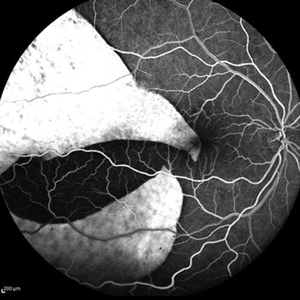

Giant RPE rip

Sep 5 2021 by Hemanth Murthy, MBBS, MD, FASRS

Autofluorescence of a 50 year-old patient with spontaneous giant RPE rip.

Photographer: Mr Veda Vyas

Imaging device: Heidelberg HRA

Condition/keywords: RPE-rip